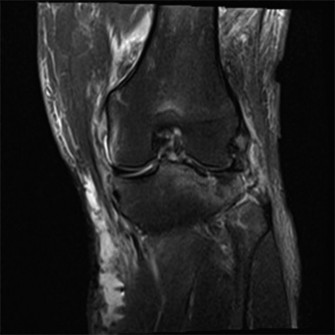

A 48-year-old woman presents to the emergency department complaining of acute left knee pain and inability to…

A 48-year-old female patient presents with anterior left knee pain. She has had a history of recurrent patell…